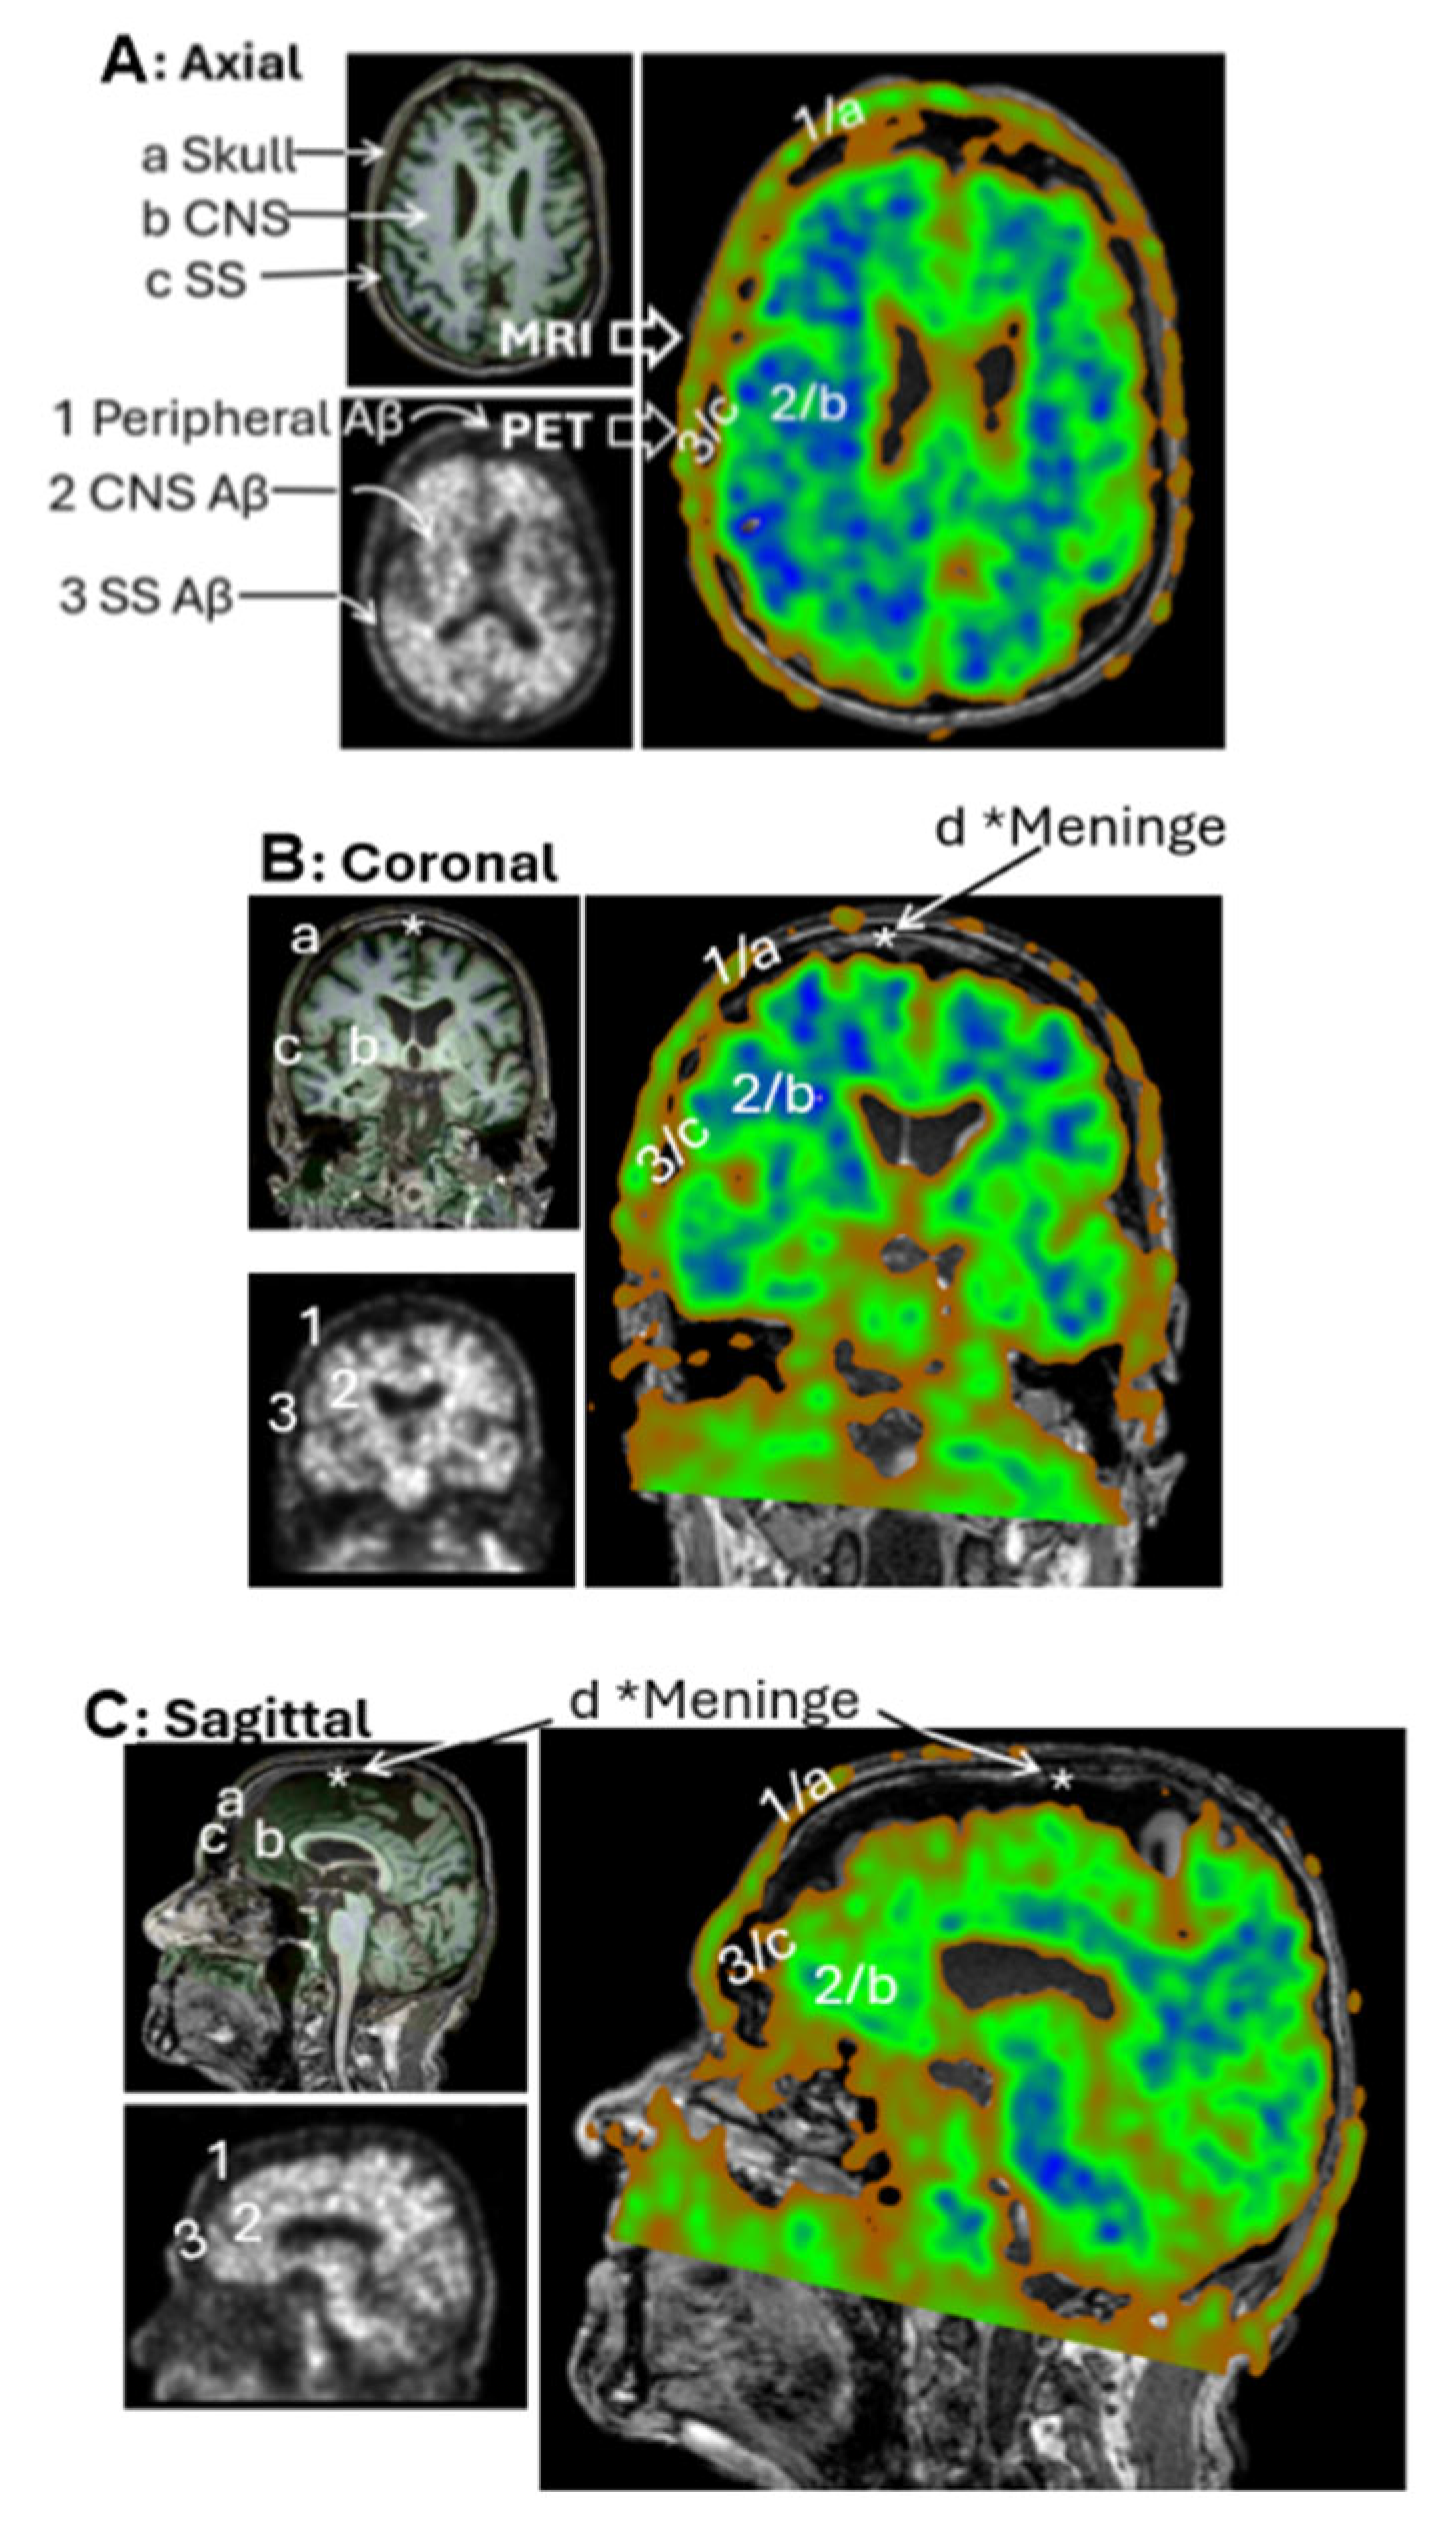

3.3. Group 2: Extracranial Aβ Signals in the Skull

In raw PET imaging, Aβ signals are detectable in both the brain parenchyma and extracranial regions. However, extracranial signals have largely been overlooked and remain poorly characterized. To begin addressing this gap, we sought to understand the spatial relationship between extracranial Aβ deposits and anatomical structures of the head. This was achieved by co-registering PET images with MRI scans from the same individuals. Figure 4A presents an axial view of the co-registered images, revealing that extracranial Aβ deposits are spatially co-localized with the skull. This pattern of colocalization was consistently observed in the coronal (Figure 4B) and sagittal (Figure 4C) views. These findings suggest that PET signals in superior regions are anatomically associated with the skull, rather than with meningeal structures.

Next, we investigated whether Aβ signals in the superior skull region exhibited organized patterns or were randomly distributed, as typically seen with plaque deposition. We observed that Aβ concentrations in the skull were lower than those in the brain parenchyma, as indicated by green coloration on the intensity scale. To isolate Aβ signals in the skull, we carefully defined ROIs in the superior regions, explicitly excluding cranial Aβ signals from the axial, coronal, and sagittal planes of the brain parenchyma.

Figure 5A illustrates a representative ROI selection strategy, with imaging dimensions of 52 slices in the anteroposterior (AP) direction, 47 slices in the right-left (RL) direction, and 3 slices in the inferior-superior (IS) direction. Figure 5B displays this extracranial ROI, finding that Aβ signals were spatially organized into distinct network-like patterns across the superior skull. Interestingly, these signals were not densely clustered as in the cranial regions. Several areas as labeled a, b, c, and d in the 3D visualization, showed no detectable Aβ signal. Due to the low concentration, the contrast against the black background was dim, making visualization challenging. To enhance clarity, the images were reprocessed using Fiji ImageJ (Figure 5B(II)), which improved the visibility of both the canal-like networks and the Aβ-free regions. In conclusion, low concentrations of Aβ were detected in the skull, forming organized canal-like networks that extended across the observed regions.

Figure 4. PET/MRI Coregistration. Representative MRI (left top panels) and PET scans (left bottom panels) from the CU-3 individual. Coregistration was conducted with 3D Slicer to set PET as the moving image (blue-green right panels) and MRI as the fixed reference (dark-gray right panels). Anatomical regions identified on MRI include a—Skull, b—Central nervous system (CNS), c—Subarachnoid space (SS), d—Meninges. Corresponding regions identified on PET include 1—extracranial Aβ signal, 2—CNS signal, 3—SS signal. Subpanels: (A) Axial view, (B) Coronal view, (C) Sagittal view. Extracranial Aβ signals are spatially aligned with the skull, not the meningeal regions.